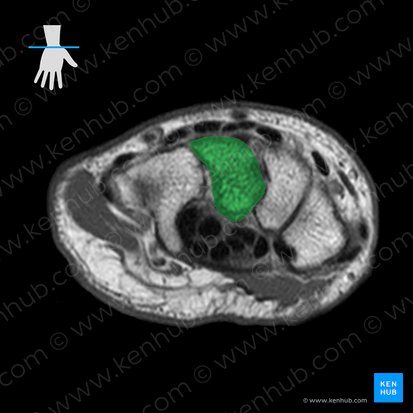

Capitate bone

The capitate bone is the largest of the eight carpal bones found in the hand.

It is a head-shaped bone located in the distal row of the carpal bones proximal to the second, third, and fourth metacarpal bones. The capitate bone is classified as a short bone. A short bone is a bone that is roughly shaped as a cube with almost equal length, width, and thickness.

The capitate bone has a head, and a rounded extremity referred to as the base. The head of the capitate bone projects into the concavity formed by the lunate and scaphoid bones.

The capitate bone also has multiple articular surfaces. The proximal surface articulates with the scaphoid and lunate. The distal surface articulates with the base of the third metacarpal. It has smaller articulations with the base of the second and fourth metacarpal bones. The medial surface is the largest articular surface for the hamate bone, while the lateral surface articulates with the trapezoid.